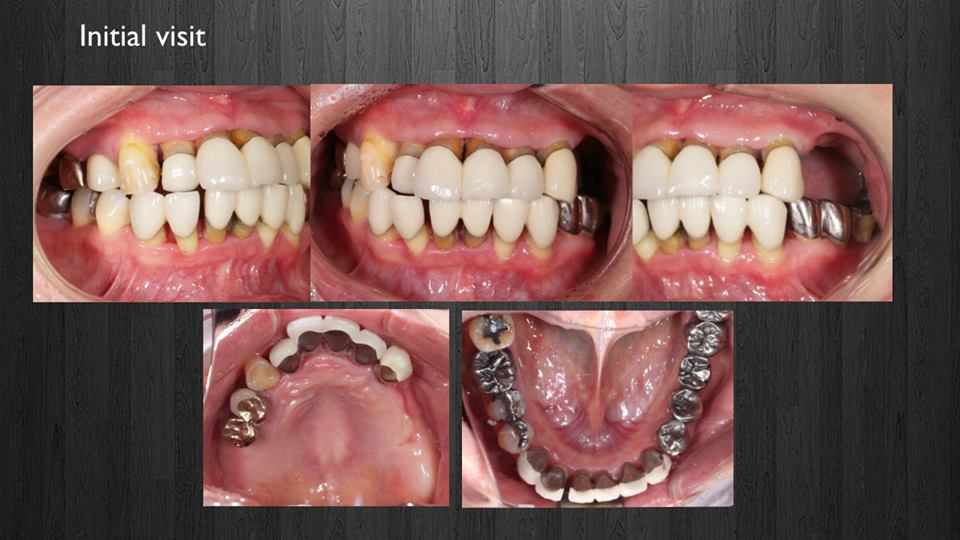

< 症例2 >

- 治療期間:28ヶ月

- 治療回数:145回

- 治療歯数:28歯

- 費用:全顎矯正治療80万円 インプラント治療:195万円 上部セラミック:300万円

- リスク:メンテナンスを怠ると、インプラント周囲炎になる可能性があります。

- インプラント手術には合併症が伴う場合があります。

- 治療期間は治癒の状態により前後する場合があります。